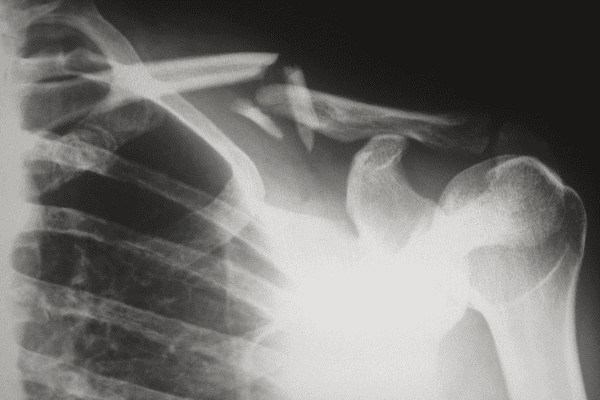

Bones & Joints Injury Claims

Bones & Joints injuries are those which involve the treatment of damage or deformation of bones, ligaments, joints and muscles. Although the vast majority of these injuries are treated successfully some are not and these are likely to result in problems for patients.